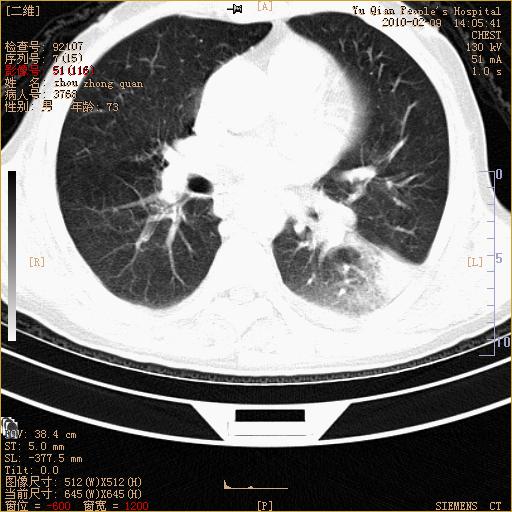

男性,73岁,咳嗽咳血数天,诊为肺ca伴左肺下叶后段阻塞性炎症、肺不张妥否?

右下肺有转移?

左下肺中央型肺癌伴结段形肺不张,左侧胸腔积液,纵隔内见部分增大淋巴结(反应性增生或转移)

左下基底干支气管明显变窄。

左肺下叶基底段支气管狭窄,左肺门增大,左肺下叶团片状病灶。中心型肺癌伴柱塞性炎症可能大,建议支气管镜检查。

左下肺中央型肺癌伴节段性肺不张,左侧胸腔积液,纵隔内见肿大淋巴结

左下基底段支气管变窄。建议进一步纤支镜检查。

1、左肺下叶后基地段肺癌伴阻塞性炎症,左下肺门淋巴结转移。2、左侧胸腔积液。